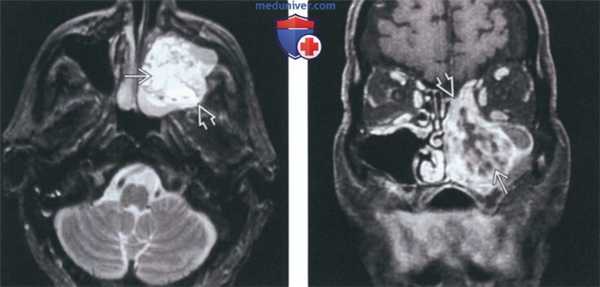

(Слева) На аксиальной МРТ (Т2 ВИ FS) определяется амелобластома верхней челюсти с солидным и кистозным компонента ми, выглядящая многокамерной. Обратите внимание на типичный гиперинтенсивный Т2 сигнал в кистозных компонентах и вздутие задней стенки верхнечелюстной пазухи.

(Справа) На корональной MPT (Т1 ВИ C+ FS) у этого же пациента определяется контрастное усиление перегородок, обычно наблюдающееся при амелобластоме. Местно агрессивную природу этой опухоли доказывает ее распространение в полость носа и ячейки решетчатого лабиринта.

(Слева) На аксиальной МР-томограмме (STIR) визуализируется крупная амелобластома нижней челюсти, в составе которой находится массивный кистозный компонент (с правой стороны) с наличием уровней «жидкость-жидкость». Обратите внимание на многокамерный компонент с гиперинтенсивным сигналом на Т2ВИ (с левой стороны).

(Справа) При МРТ Т1ВИ FS сКУ в аксиальной проекции у это го же пациента с амелобластомой нижней челюсти определяется выраженное контрастное усиление стенок крупной однокамерной кисты, расположенной справа. Видны также множественные кисты меньшего размера с левой стороны.

(Слева) При MPT Т2ВИ с КУ в аксиальной проекции у пациента с амелобластомой верхней челюсти определяется солидный и кистозный (многокамерный) компонент. Обратите внимание на типичный интенсивный (Т2ВИ) сигнал в кистозном компоненте, а также экспансивное воздействие опухоли на заднюю стенку верхнечелюстной пазухи.

(Справа) На корональной (T1ВИ) томограмме с контрастным усилением и жироподавлением у этого же пациента определяется характерное контрастное усиление перегородок. Местно агрессивный характер амелобластомы также подтверждается ее распроаранением в полость носа и ячейки пазухи решетчатой кости.